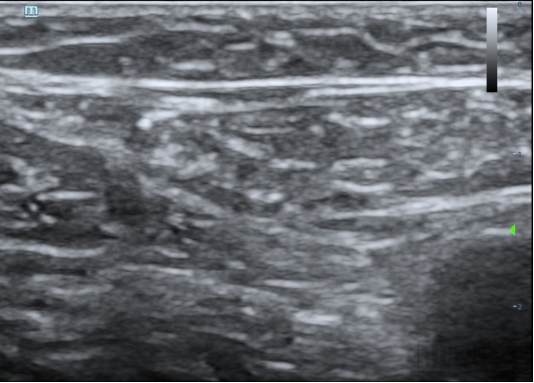

本次臨床試驗的入組患者為63歲男性,其靜脈曲張符合本臨床試驗方案入選入排標準。經(jīng)上海交通大學醫(yī)學院附屬第九人民醫(yī)院陸信武主任團隊對患者評估,選擇使用恩盛醫(yī)療自主研發(fā)的VeSeal靜脈閉合系統(tǒng),在超聲影像的引導下采用微創(chuàng)介入的方式將病變血管閉合,整個手術時間不到半小時。

據(jù)介紹,VeSeal靜脈閉合系統(tǒng)不同于其他臨床研究,VeSeal還配備了輸送導絲及導管鞘管等標準配件,注射導管在超聲下實時可見,鞘管具有標尺,手術過程無需其它配件,方便臨床醫(yī)生快速、便捷、高效的將病變血管閉合。